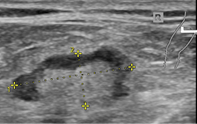

Abbildung 1 zeigt einen physiologischen, submandibulär gelegenen Lymphknoten ohne entsprechende Vergrößerung oder anderen auffälligen Kriterien.

Die Berechnung des sog. Solbiati-Indexes sehen Sie in Abbildung 2. Der Lymphknoten war formal mit 13 mm leicht vergrößert, andere Auffälligkeiten zeigten sich jedoch nicht. Es handelt sich um einen benignen, inguinal rechts gelegenen Lymphknoten.